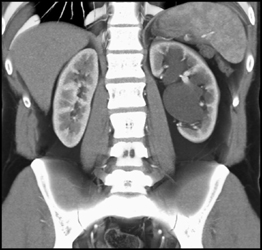

1 Cm Renal Cell Carcinoma